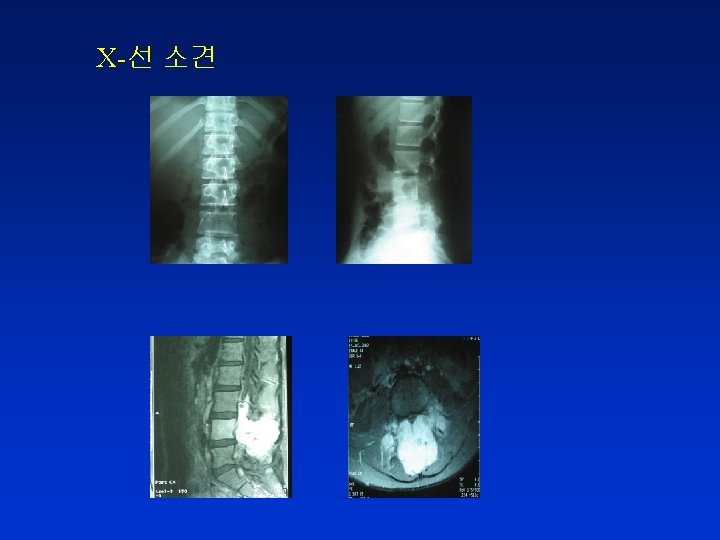

증례 6 14세 여자 진단명 : Osteogenic sarcoma with multiple lung metastases 주소 : 1) pain on right leg 2) back pain 3) voiding difficulty 4) severe coughing 현 병력 : 2002년 8월 Osteogenic sarcoma on right distal tibia 진단 chemotherapy 없이 지내다가 상기 증상 발생, 심해져서 내원 검사실 검사 소견 CBC : Hb 8. 7 g/d. L, WBC 3, 600 (Seg N 55%), PLT 223, 000 /u. L Blood Chemistry : WNL

진 단 Osteogenic sarcoma Metastasis on the pedicle of L 4 spine with mild spinal cord compression

치 료 1) MS contin 60 mg Po bid, every 12 hours 2) external beam radiation therapy on lumbar spines 3) dexamethasone injection